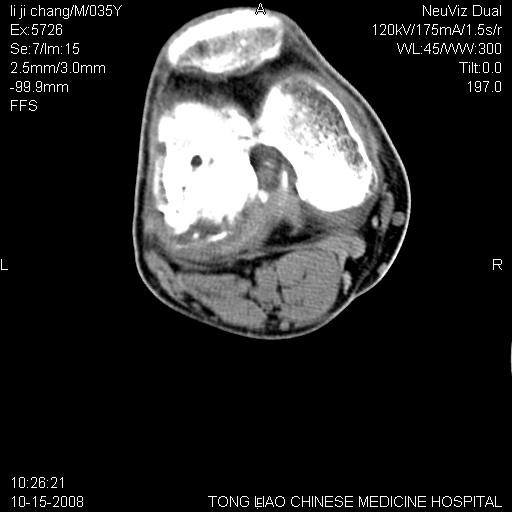

男,35岁,骨科诊断骨性关节炎。继往使用过激素,现股骨头坏死。膝关节病变,请会诊

一元论-----亦考虑为坏死

支持考虑无菌坏死

支持无菌坏死伴退行性骨关节病.

剥脱性骨软骨炎:是一种关节下软骨及软骨下骨缺血性坏死。

支持 无菌性坏死伴退行性骨关节病。